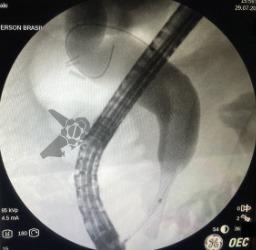

Posteriormente submeteu-se à Ecoendoscopia com punção da lesão que confirmou se tratar de Adecocarcinoma mal diferenciado. Em virtude do estadiamento e condições clínicas do paciente, foi definido em avaliação multidisciplinar por tratamento oncológico clínico (não cirúrgico) com drenagem da obstrução biliar maligna (OBM) através de prótese metálica autoexpansível (PMAE).